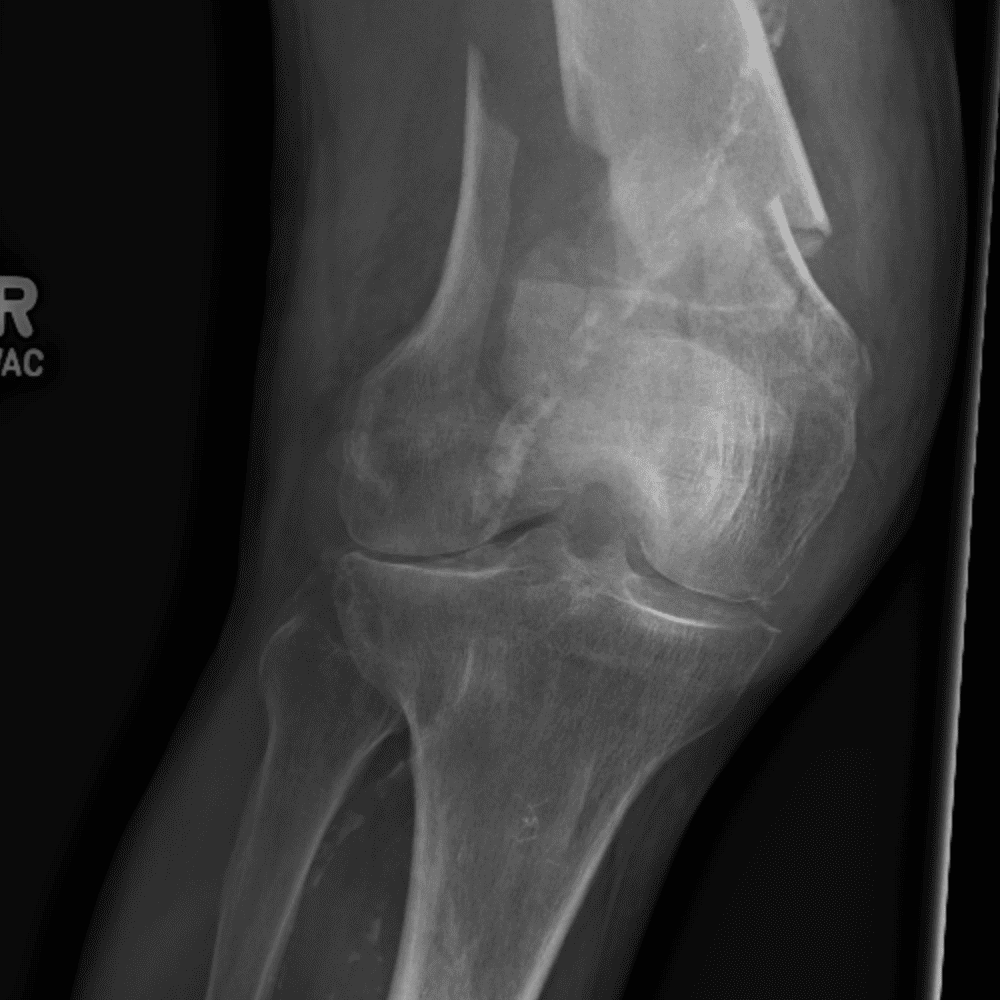

Simula o plantão incluindo casos sutis ou difíceis e alguns normais.